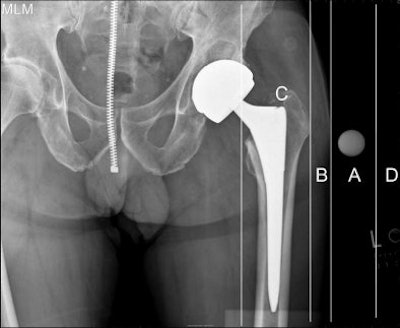

In the study, the frequency of correct versus incorrect marker placement was calculated for both types of markers. Four positions were assessed:

- The correct placement (A) at the level of the greater trochanter

- A second position (B) with soft-tissue overlap of the marker

- A third position (C) with bony overlap of the marker

- A fourth position (D) (the second most accurate) in which there was no contact between the marker and soft tissue

| Digital hip image above demonstrates four possible positions for x-ray templating markers. Markers placed in the area represented by position A, at level of the greater trochanter, proved to be the most accurate, according to the authors. Image courtesy of Dr. Thomas Barber. |